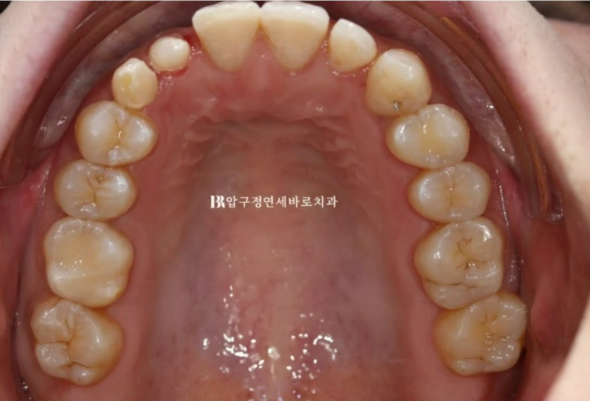

오른쪽 송곳니 파란 화살표 부분에 유치가 남아있는 환자분입니다.

영구치 송곳니가 없어서 그렇습니다.

반대쪽 같은 부위 정상 송곳니에 비하여 사이즈가 많이 작습니다.

유치라 어쩔 수 없지만 앞니 부분교정으로 적절하게 공간을 벌어주면 무삭제 라미네이트 젤라미로 송곳니만큼 사이즈를 회복할 수 있습니다.

가운데 말고 옆 앞니에 얼룩덜룩한 부분은 레진으로 왜소치를 치료한 흔적입니다.